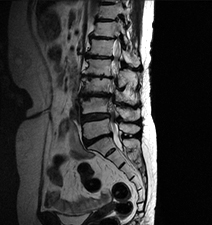

척추관협착증 이미지

진단은 방선 소견으로 주로 확인되는데 평면 사진으로 척추간 간격을 확인할 수 있고, 동적 촬영으로 불안정성 확인을 할 수 있는 단순 방사선 촬영, 눌린 부위를 나타낼 수 있는 척추강조영술, 척추관의 골조직의 크기와 모양을 정확히 알 수 있고 신경관도 관찰 할 수 있으며 전산화 단층 촬영술, 그리고 골조직외에 연부조직 사이의 상태까지 잘 알 수 있는 자기공명영상(MRI)등을 이용할 수 있습니다.

MRI는 뼈와 신경, 디스크를 완전히 구분하여 보여주어 목 디스크의 진단을 더욱 세밀하고 쉽게 할 수 있습니다.